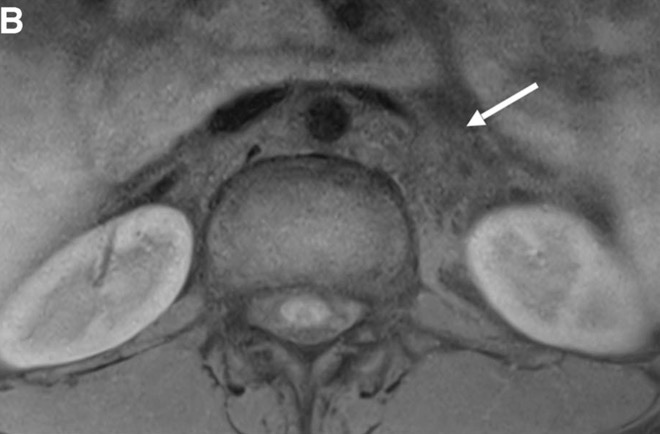

c. Lipomatose encéphalocraniocutanée (ECCL): peau, yeux, SNC)

ECCL: